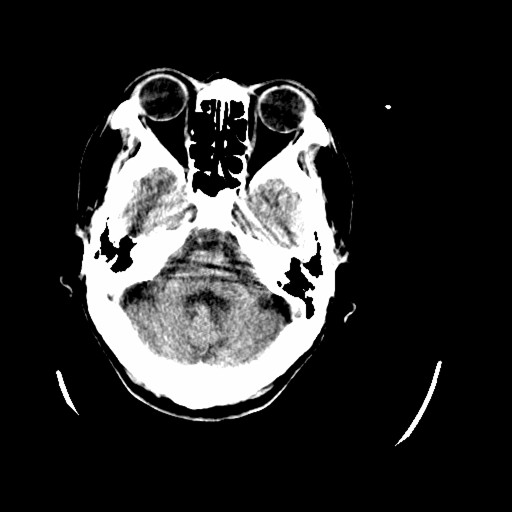

标题: CT16233:女,44岁,智障多年,现感头痛 [打印本页]

标题: CT16233:女,44岁,智障多年,现感头痛

小脑有啥病变?

橄榄桥小脑萎缩.左侧小脑脚腔梗.

为什么不考虑发育畸形呢

1)小脑萎缩。2)小脑蚓部发育不良。

橄榄桥小脑萎缩可能,建议mri进一步检查以进一步排查。

小脑萎缩征,原因待定.

橄榄桥小脑萎缩